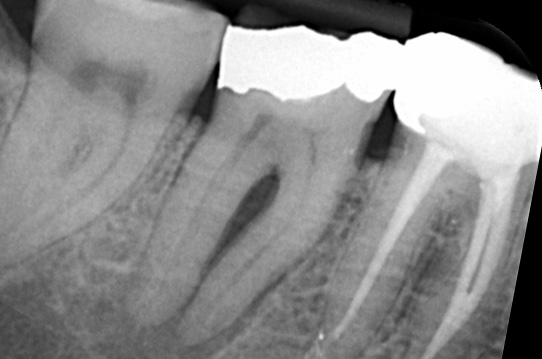

Gallery - Root Canal Treatment

Case 6

Before After